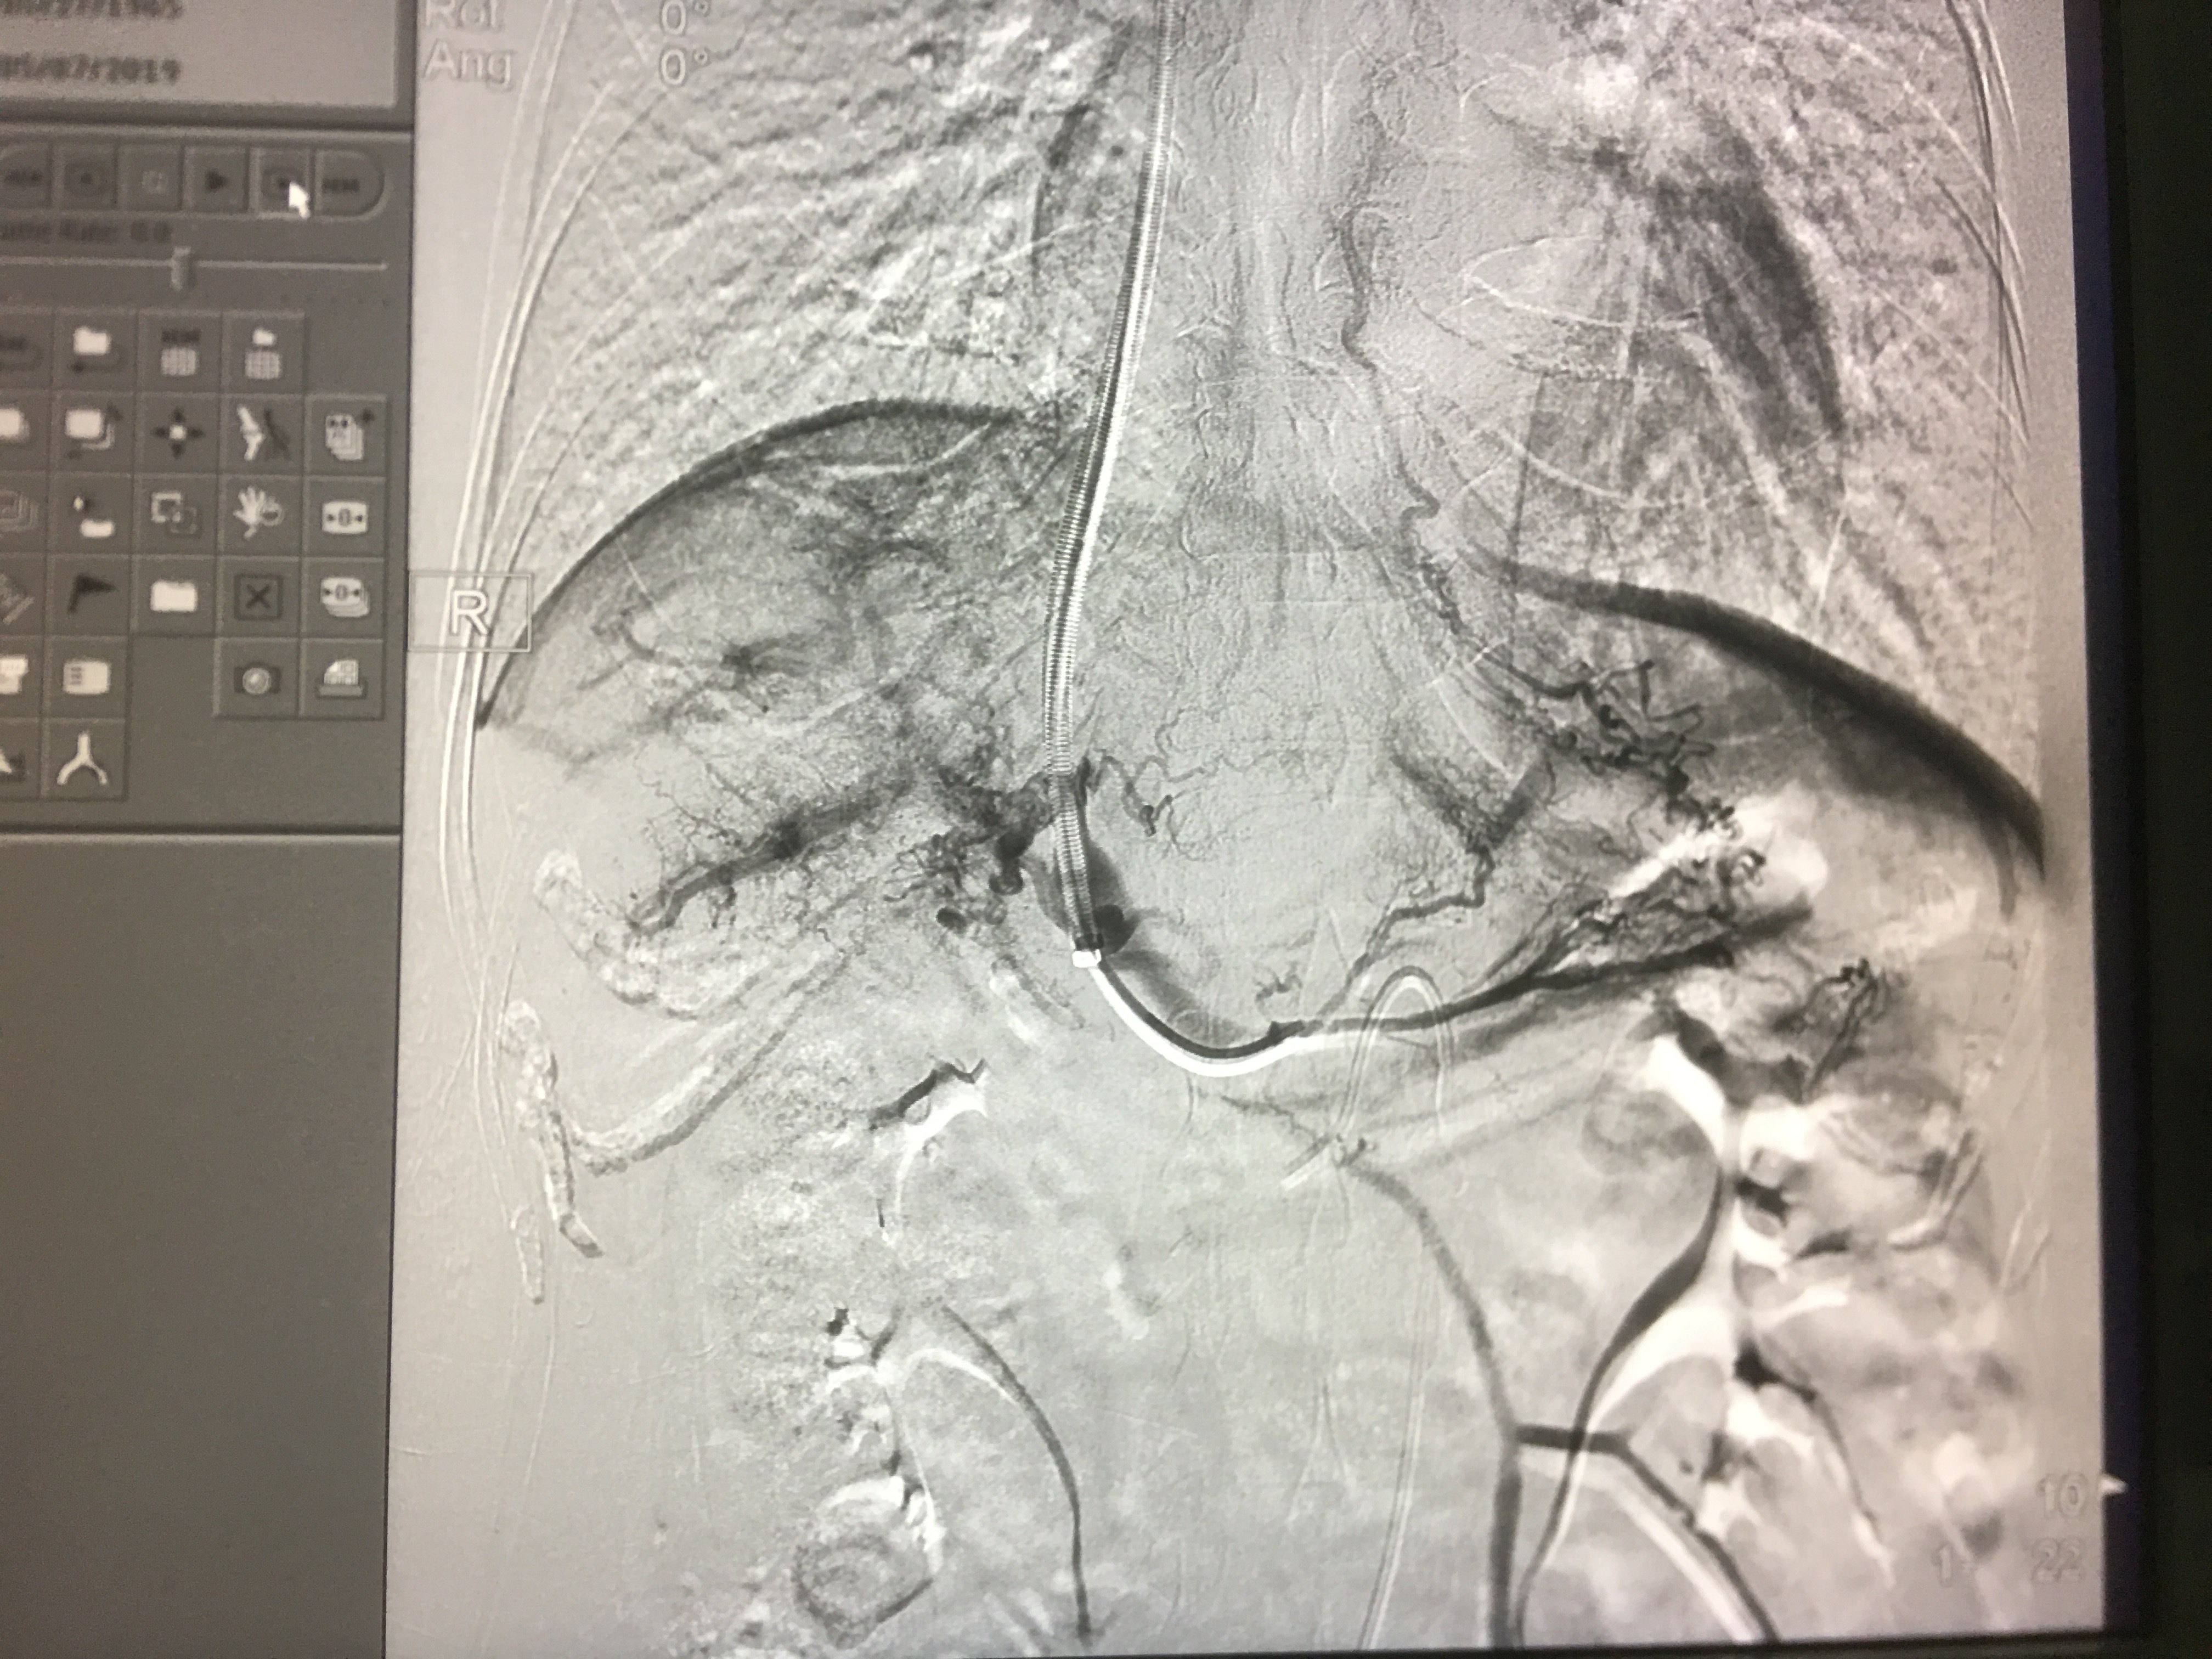

间接门静脉造影以期获得肝静脉和门静脉之间的关系。